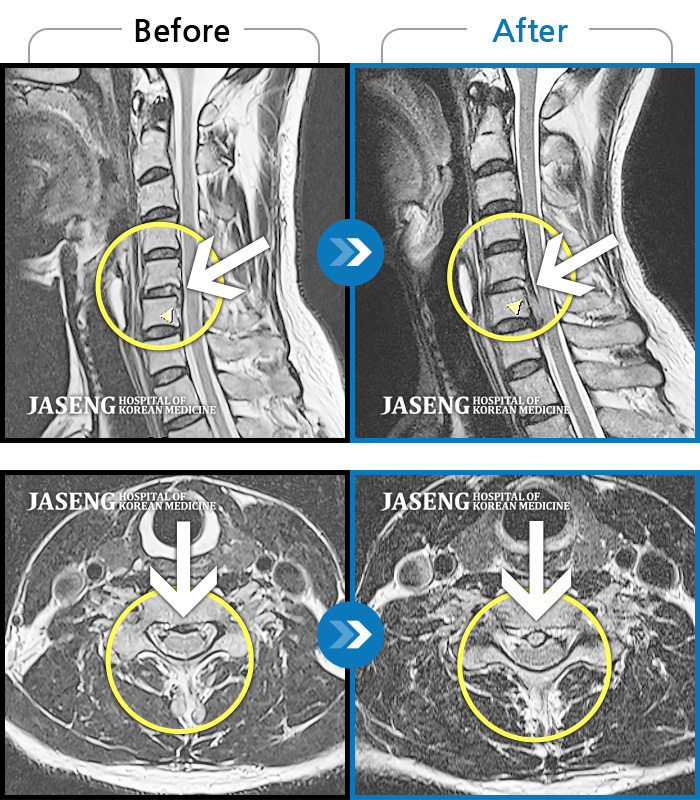

목디스크

광주 · 김동은 원장

후경부에서 견갑골까지 이어지는 묵직한 통증과 좌측 상지부위 저림

촬영시기

2018.03.12 ~ 2020.12.21

2020.12.24